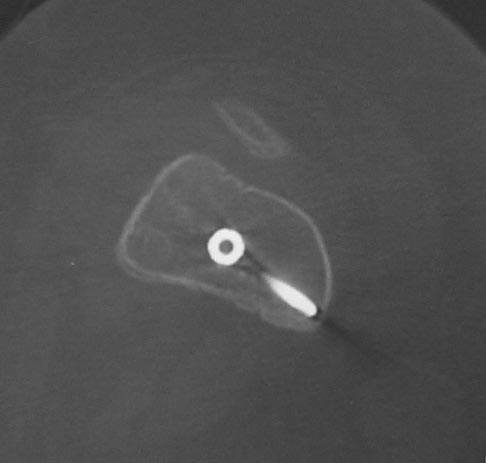

Уважаемые коллеги. Хотелось бы выслушать мнения и советы по представленному случаю. Пациент 42 лет, вес 130 кг, рост около 160 см, сахарный диабет в легкой форме (впервые выявлен после травмы). Травма в феврале 2011 г. - упал с мотоцикла на отдыхе за рубежом. По возвращении в Россию был прооперирован в несколько этапов: в марте 2011 г. - остеосинтез обеих костей правого предплечья пластинами по поводу открытого перелома; интрамедуллярный остеосинтез правого бедра; остеосинтез проксимального конца правой большеберцовой кости. В апреле 2011 г. был доставлен 1 блокирующий винт в дистальное отверстие гвоздя и выполнена пластика крестообразных и наружной боковой связок левого коленного сустава. В феврале 2012 г. были удалены фиксаторы с проксимального конца правой большеберцовой кости и выполнена пластика крестообразных и наружной боковой связок правого коленного сустава. За это время пациент смог начать ходить, сначала с костылями, а затем - без дополнительной опоры. Летом 2013 г. решил укрепить ноги с помощью подъемов пешком на пятый этаж. В результате - усталостная рефрактура правого бедра и перелом интрамедуллярного гвоздя. 09.09.2013 - реостеосинтез латеральным бедренным гвоздем с пластикой костной аутостружкой + СhronoS. Сейчас, через 6 мес после операции, может ходить без дополнительной опоры, периодически беспокоит болезненность в области правого бедра. На сегодняшних КТ - отсутствие признаков консолидации. Нужно ли что то делать и, если да, то что? Рассматриваемые варианты: повторная костная пластика дефекта; доставить блокирующие винты (самый проксимальный винт был удален через 3 мес после операции). Еще раз менять гвоздь не хотелось бы. На представленных снимках: бедро в 2011 г., через несколько мес после операции; в 2012 г., на стадии консолидации; со сломанным гвоздем; сразу после повторной операции (3 рентгенограммы). Все КТ - сегодняшние. Заранее спасибо за ответы.

А какой диаметр последнего стержня? По представленным снимкам кажется, что тонковат...?

Второй гвоздь был на 2 см длиннее и на 1 номер толще предыдущего. По-моему десятка.В принципе какая разница? Впечатление о том, что тонковат, ведь не зависит от реальной толщины гвоздя. Канал не рассверливал. Но забивал с трудом.

Мне тоже показалось, что тонковат. Но, раз операция нежелательна, надо ждать и лечить консервативно. При неуспехе - на мой взгляд, замена стержня на более толстый с рассверливанием канала и, возможно, костной пластикой.

Сергей, а ?ожно по подрбнее о костной пластике при в сентябре 2013 приреостеосинтезе. Что это была за пластика? доступ? было ли рассверливание? диаметр гвоздя?

ждать-не ждать? Срочности нет, подождать можно, но активно, т.е. оценить клиническую и рентгенологическую динамику: два месяца назад, сейчас и еще через пару месяцев. Уменьшатся боли, появится более убедительная мозоль - ждите и наблюдайте дальше. Отсутствие положительной динамики можно приравнять к отрицательной динамике. Очевидно, что здесь имеют место быть обе проблемы: биологическая -мозоль слабая и механическая - тонкий гвоздь, недостаточная стабильность. Тогда -удаление, рассверливание (очень аккуратное, по 0.5 мм шаг, острыми фрезами, чтобы не пожечь кость - кортикал толстый и довольно прочный). Для 130 кг диаметр гвоздя минимум 12 мм, лучше больше. Здесь можно и 14мм гвоздь взять и блокировать дистально винтами 6,0 мм. Открывать перелом и пытаться делать еще пластику экстрамедуллярно не стоит. Рассверливания будет достаточно.